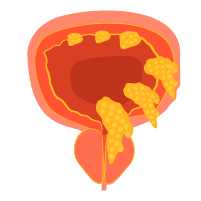

Prosedur Pengangkatan Kandung Kemih Melalui Cystectomy

Memiliki gejala terkait penyakit kandung kemih, termasuk kanker, mungkin tidak mengenakkan. Selain mengganggu kehidupan sehari-hari, Anda juga perlu menjalani sejumlah pengobatan yang menyita waktu. Salah satu pengobatan yang terkait dengan kandung kemih ini adalah cystectomy. Apa itu dan bagaimana dokter menjalankan prosedur ini? Definisi cystectomy Cystectomy adalah prosedur pembedahan untuk mengangkat kandung kemih. Pengangkatan kandung kemih ini […]